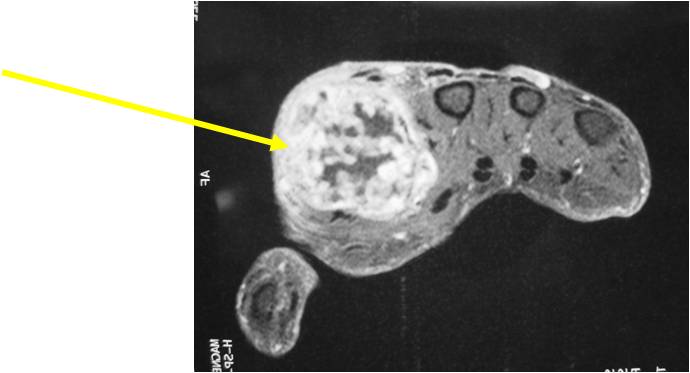

- MRI

- Lobulated margin

- Marked increased intensity long TR images

- Calcified chondroid – low intensity all sequences

MRI:

- Lobulated margin (Lobular Growth Pattern)

- T1 Weighted Images: Intermediate Signal Intensity

- Calcifications will be low signal

- T2 Weighted Images: High Signal Intensity

- High water content shows as high signal on T2 weighted images

- Calcifications will be low signal

- Marked increased intensity long TR images

- Calcified chondroid – low intensity all sequences

- There should never be any cortical destruction nor a soft tissue component. If this exists then the tumor must be a chondrosarcoma.

- Endosteal scalloping and cortical expansion is acceptable for phalangeal tumors. In most benign long bone cartilage tumors there is minimal endosteal scalloping but there should be no cortical expansion nor thickening. There should be no cortical destruction and no soft tissue component associated with an enchondroma. Cortical destruction, periosteal thickening, cortical expansion and a soft tissue component indicates a chondrosarcoma of the long bone.